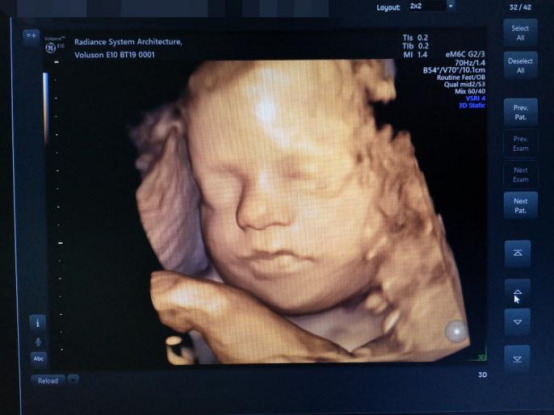

3. 产前超声精准筛查

开展早/中孕期胎儿出生缺陷筛查,配四维高端设备,结合规范流程,提升胎儿畸形检出率,护航母婴安全。